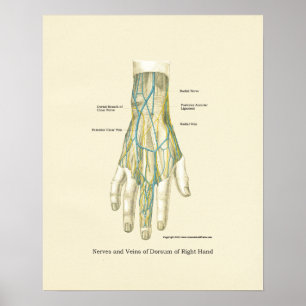

Poster interno da anatomia da mão & do pulso

Preço44,35 €

Poster interno da anatomia da mão & do pulso

Preço48,95 €

Poster interno da anatomia da mão & do pulso

Preço44,35 €

Poster interno da anatomia da mão & do pulso

Preço48,95 €

Poster interno da anatomia da mão & do pulso

Preço48,95 €

Poster de Anatomia Interna da Mão e Pulso

Preço44,35 €